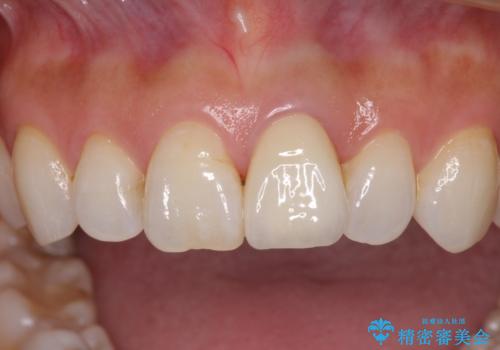

変色とともに、捻れていたことも気になっていたので、その両方を解決させることとしました。

オーダーメイドタイプのクラウンを選択いただいたので、まるで天然の歯と見間違うほど自然に仕上がり、患者様には大変満足していただきました。